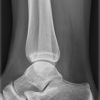

Oberes Sprunggelenk a.-p. (1. Ebene)

Technik

• FDA: 1,05 m

• Ausgangsformat: 18/24

• Übertischaufnahme

Indikation

Fraktur, Bandverletzungen, Luxation

Lagerung

sitzend/ liegend auf Tisch

gestreckte Bein nach innen rotieren, sodass Malleolus medialis und lateralis auf einer Höhe sind

(ca. 15-20° - Zeigefingertest)

Fuß anziehen, möglichst senkrecht zum Unterschenkel

Zentralstrahl

senkrecht

Querzentrierung: Gelenkspalt

Längszentrierung auf Objektmitte

Einblendung

proximal 5 QF ab ZS, lateral 1 QF

Qualitätskriterien

Frei einsehbares oberes Sprunggelenk, insbesondere im Bereich von Innen- und Außenknöchel und der tibiofibularen Syndesmose.